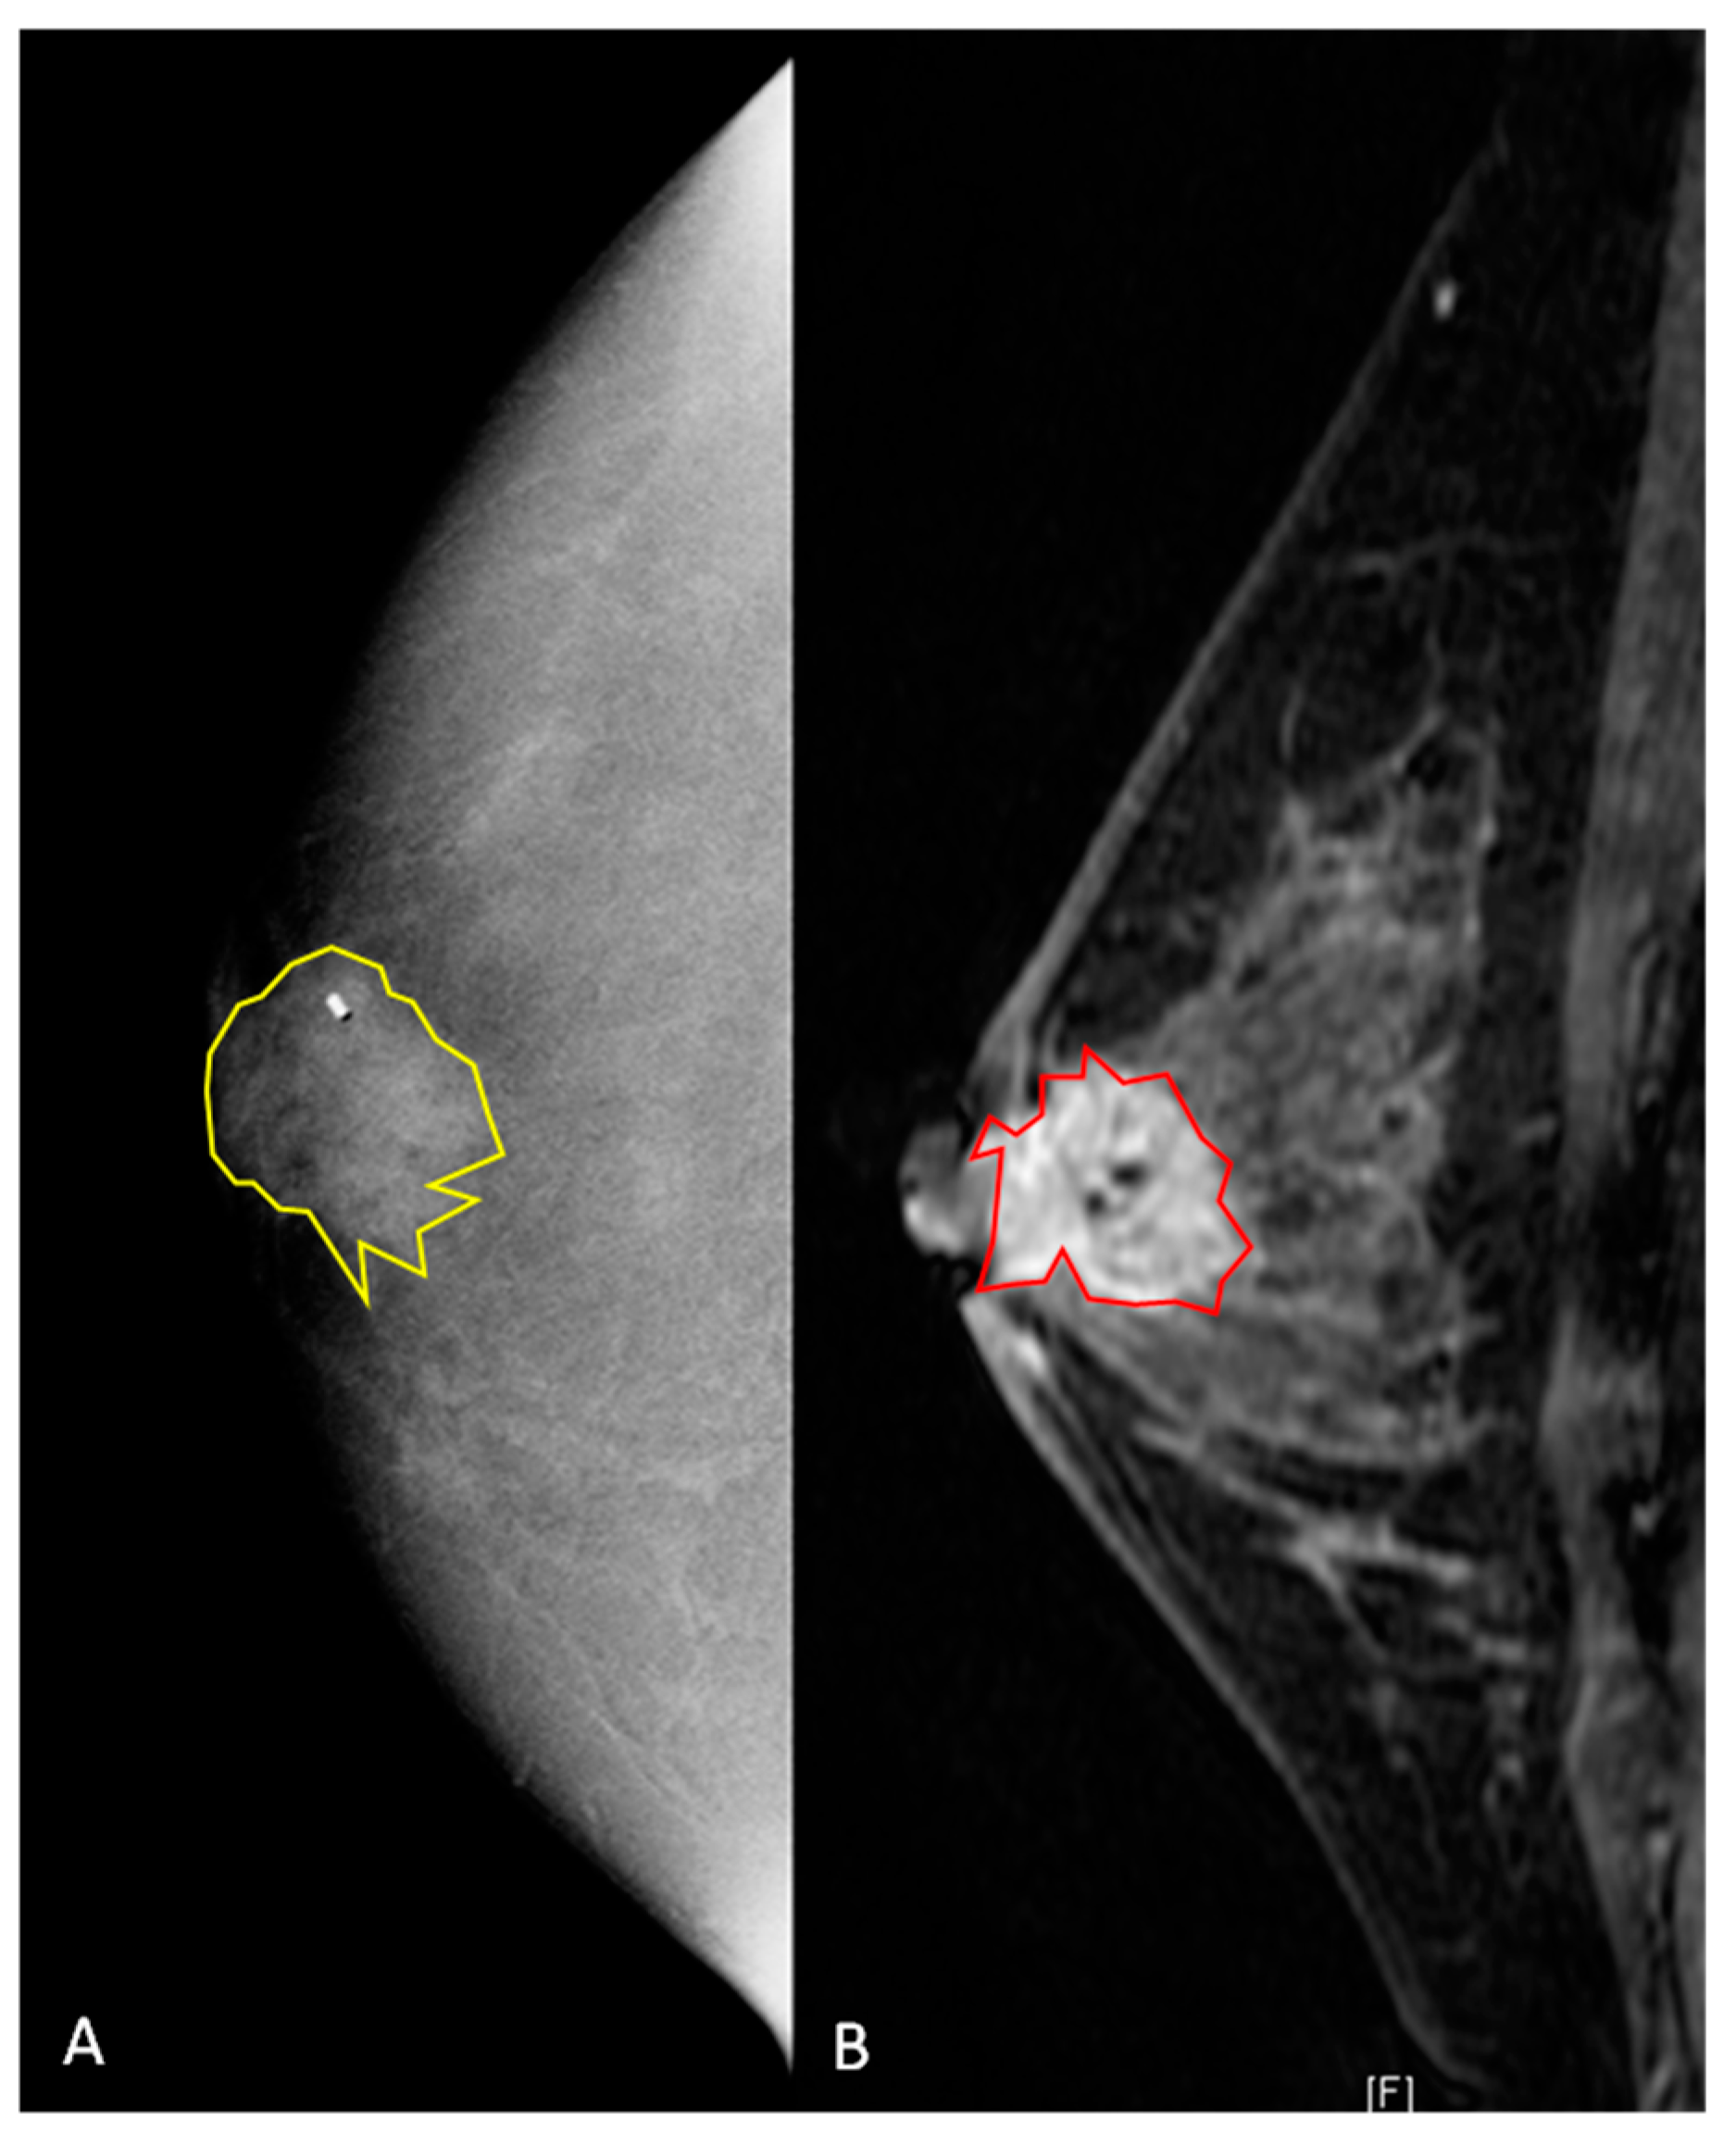

2.4. Segmentation of Lesions